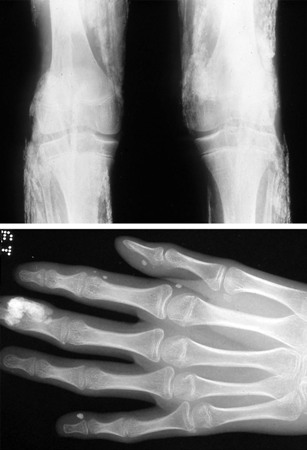

X-rays

Indicated in the context of suspected trauma, orthopaedic hip conditions and non-accidental injury.

Films of long bones should include anterior posterior (AP) and lateral views of shaft and joints at both ends, and views of both sides of the bone to allow comparison with the healthy side.

Hip x-rays need to include AP and frog views (to exclude slipped capital femoral epiphysis).

A skeletal survey may be useful in the evaluation of skeletal dysplasia or non-accidental injury. Local policies should be followed. It should be reviewed by an expert radiologist to distinguish changes from normal variants.[Figure caption and citation for the preceding image starts]: Non-accidental injury with 'hot spots' on bone scan due to multiple fracturesFrom Dr Foster's personal collection; used with permission [Citation ends].